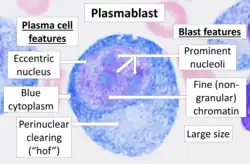

Immature plasma cells

The most immature blood cell that is considered of plasma cell lineage is the plasmablast.[11] Plasmablasts secrete more antibodies than B cells, but less than plasma cells.[12] They divide rapidly and are still capable of internalizing antigens and presenting them to T cells.[12] A cell may stay in this state for several days, and then either die or irrevocably differentiate into a mature, fully differentiated plasma cell.[12] Differentiation of mature B cells into plasma cells is dependent upon the transcription factors Blimp-1/PRDM1, BCL6, and IRF4.[10]